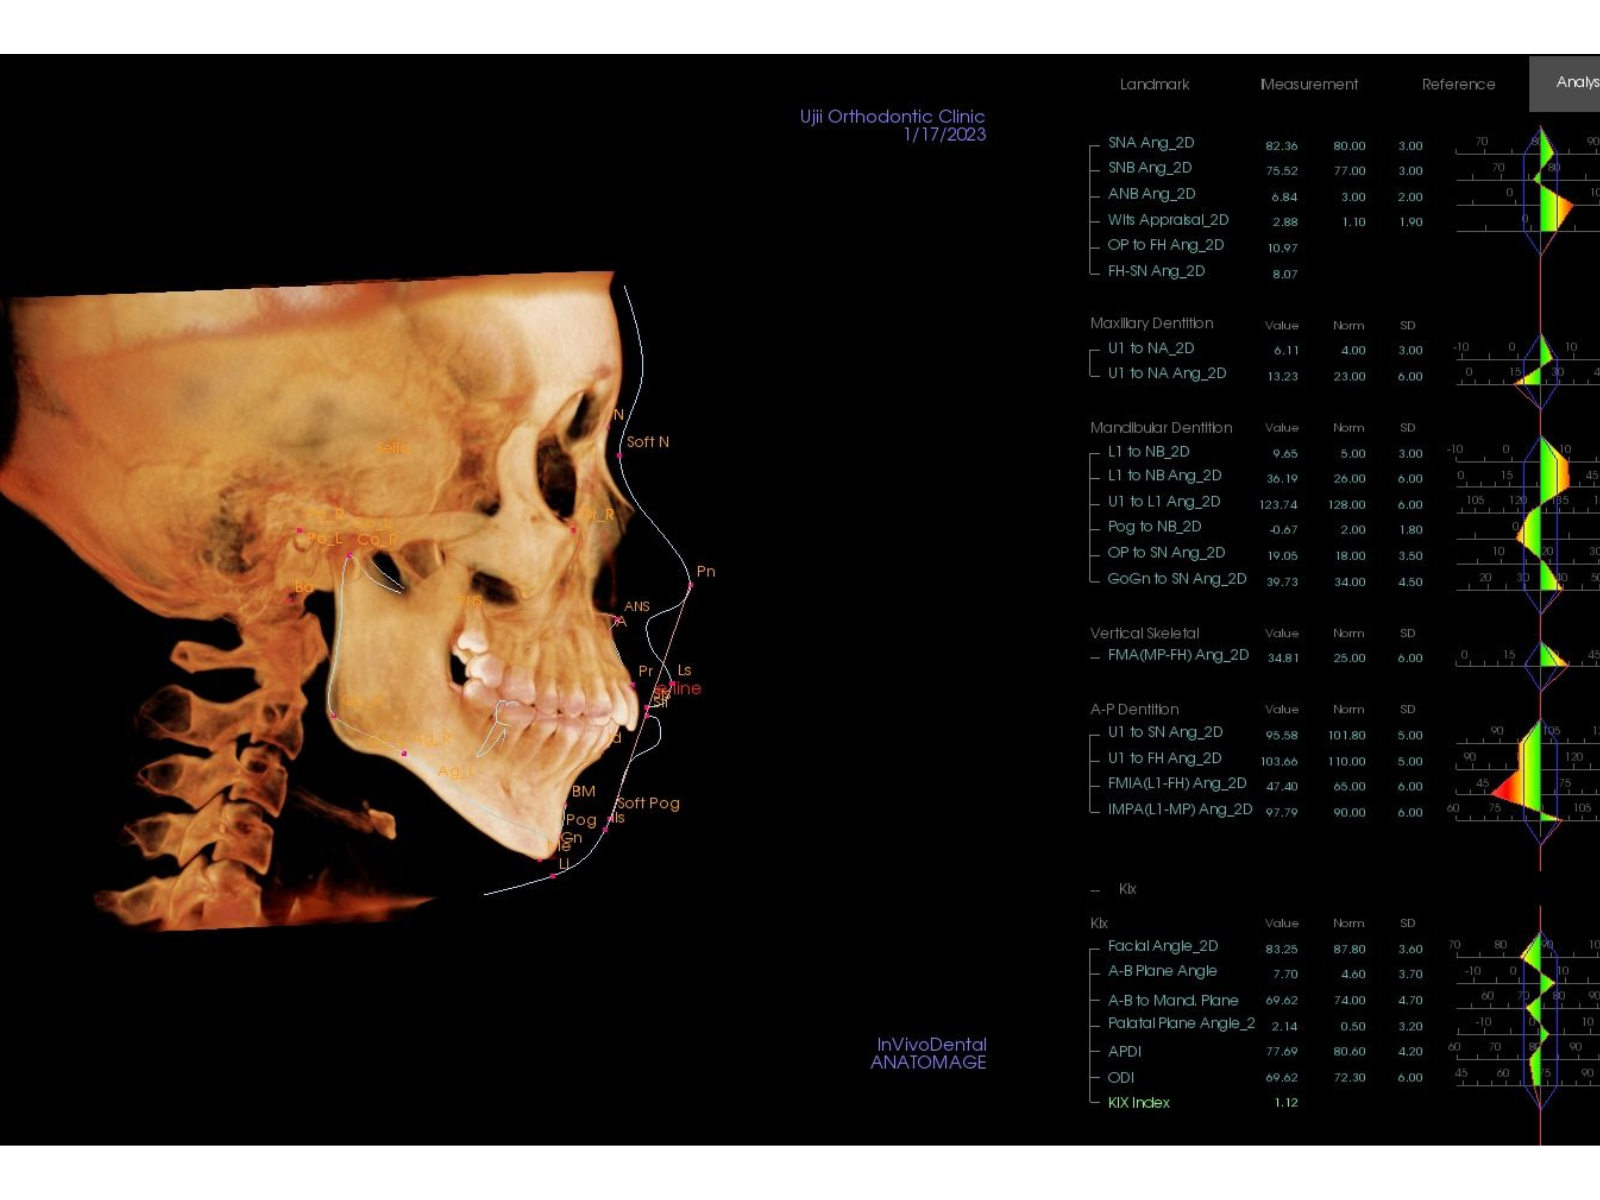

CT・セファロ・アイテロのデータが揃った段階で、この患者さまの口元の状態を客観的に分析しました。

結論は、シンプルでした。

口元をしっかり下げるためには、(1)上下の小臼歯4本を抜いてスペースを作る、(2)そのスペースを使って歯列全体を後方に動かす——そしてその大きな動きを安定させるために (3)インプラントアンカーが必要という状態でした。

マウスピース矯正が悪い治療だったわけではありません。ただ、この患者さまの口元の突出量に対しては、アンカースクリューなしの非抜歯という枠組みでは、物理的に届かない範囲だったのです。

初診時セファロ分析(79-04)|奈良の矯正歯科